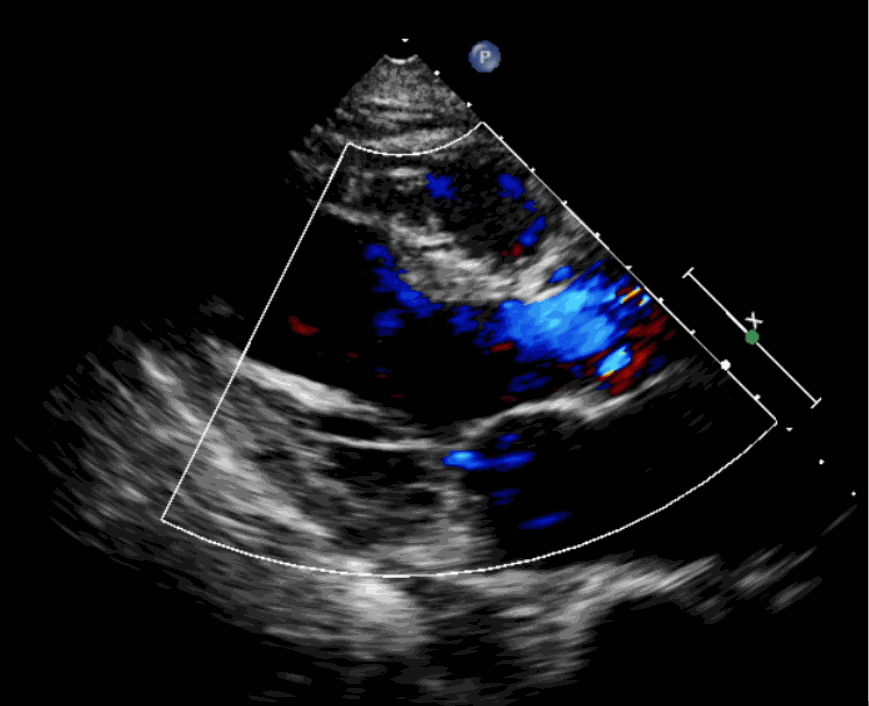

術(shù)前超聲影像圖

該例患者為62歲,女性,因“間歇性心悸、胸悶、氣短、胸痛1年,加重1周”之主訴入院。入院診斷:主動(dòng)脈瓣重度關(guān)閉不全,二尖瓣、三尖瓣輕度關(guān)閉不全,心功能III級(jí);冠狀動(dòng)脈粥樣硬化性心臟病。行心臟超聲心動(dòng)圖提示“主動(dòng)脈瓣重度關(guān)閉不全;瓣口水平以下左室下壁、后下壁搏幅減低;EF值 0.30,左房、左室大、右房大小正常高限;二尖瓣、三尖瓣關(guān)閉不全;輕度肺動(dòng)脈高壓(收縮壓42mmHg);主動(dòng)脈硬化;左室收縮功能重度減低。經(jīng)心血管外科劉洋、楊劍教授、麻醉科陳敏教授及超聲科孟欣教授等專家團(tuán)隊(duì)綜合評(píng)估,判定患者為外科手術(shù)高?;颊?。